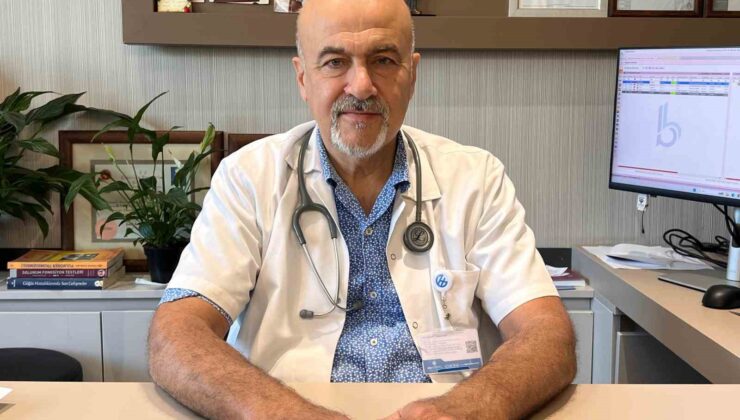

KOAH’ta erken tanı hayat kurtarıyor

KOAH’ta erken tanı hayat kurtarıyor